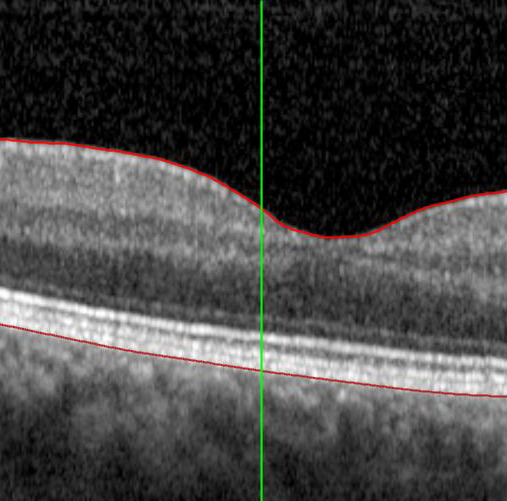

Le fait que vous ayez été dirigé vers un ophtalmologiste vous permettra d’obtenir un diagnostic formel de DMLA (ou d’éliminer d’autres affections pouvant affecter votre rétine). Les évaluations habituelles pour détecter la DMLA incluent un test de vision et un examen de la vue complet, y compris un examen de la rétine. De plus, vous devrez probablement passer un examen d’imagerie appelé tomographie par cohérence optique (TCO). Il s’agit d’un balayage laser non invasif du fond de l’œil. Il permet à votre ophtalmologiste de voir des zones de la rétine pouvant être endommagées ou en train de mourir et vérifier la présence de vaisseaux sanguins anormaux. Sur la base de ce que constate votre ophtalmologiste avec ces examens, d’autres examens d’imagerie pourraient être nécessaires.

D’autres domaines de progrès sont le diagnostic et le suivi. L’autofluorescence du fond d’œil (AF) est une technique d’imagerie utile pour obtenir une définition plus claire des zones de cellules endommagées dans les cas de DMLA sèche. Les images peuvent être associées à des algorithmes d’IA pour aider à suivre l’évolution de la maladie et surveiller la croissance des lésions. Lorsque cette technologie d’apprentissage automatique sera largement accessible à l’échelle clinique, elle nous fournira un autre outil pour surveiller les formes avancées de DMLA.